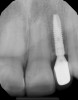

Fig 3. Radiographic scan of fused maxillary central-peg lateral incisors, teeth Nos. 7 and 8, and congenitally missing lateral incisor, tooth No. 10.

Figure 3

A 9-year-old girl, referred to a prosthodontic office by her pediatric dentist, presented with her mother’s chief complaint: “The kids are teasing her about her big front tooth.” Findings from radiographic and clinical examinations revealed fused maxillary central-peg lateral incisors, teeth Nos. 7 and 8, and a congenitally missing lateral incisor, tooth No. 10 (Figure 1 through Figure 3). An implant was selected as the ideal treatment to replace tooth No. 10 when somatic growth was complete. A diagnostic wax-up was fabricated to determine if the fused tooth could be made to resemble two teeth, using pink composite to give the illusion of an interproximal papilla. The patient was referred for an orthodontic consultation to plan for closure of the diastema between teeth Nos. 8 and 9 and achievement of proper alignment for implant No. 10. The patient was also referred to a periodontist for pretreatment assessment of the tooth No. 10 site. An endodontist was consulted should exposure of the large pulp occur during tooth preparation.